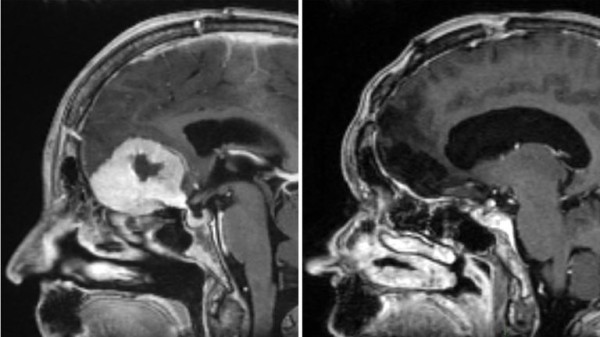

Surgeon removes large brain tumours through patients’ eyebrows in ‘world first’

A surgeon is removing brain tumours “the size of large apples” through patients’ eyebrows, in what is believed to be a world first.

Dealing with tumours at the front of the brain normally requires surgeons to remove a large portion of the skull – exposing healthy parts of the brain in the process – in what is known as a craniotomy.

Mr Giamouriadis who works for NHS Grampian said this type of surgery is not new, but he has modified it to give him “more space, through the eyebrow” allowing him “to remove very big brain tumours”.

The technique is “a game-changer and much less invasive”, he said. “Traditionally people would be left with scars across their full forehead, we avoid that with this method.”